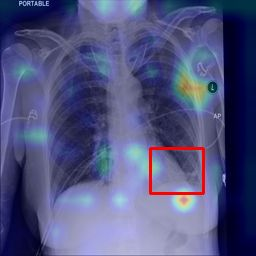

Deployments of artificial intelligence in medical diagnostics mandate not just accuracy and efficacy but also trust, emphasizing the need for explainability in machine decisions. The recent trend in automated medical image diagnostics leans towards the deployment of Transformer-based architectures, credited to their impressive capabilities. Since the self-attention feature of transformers contributes towards identifying crucial regions during the classification process, they enhance the trustability of the methods. However, the complex intricacies of these attention mechanisms may fall short of effectively pinpointing the regions of interest directly influencing AI decisions. Our research endeavors to innovate a unique attention block that underscores the correlation between 'regions' rather than 'pixels'. To address this challenge, we introduce an innovative system grounded in prototype learning, featuring an advanced self-attention mechanism that goes beyond conventional ad-hoc visual explanation techniques by offering comprehensible visual insights. A combined quantitative and qualitative methodological approach was used to demonstrate the effectiveness of the proposed method on the large-scale NIH chest X-ray dataset. Experimental results showed that our proposed method offers a promising direction for explainability, which can lead to the development of more trustable systems, which can facilitate easier and rapid adoption of such technology into routine clinics. The code is available at www.github.com/NUBagcilab/r2r_proto.